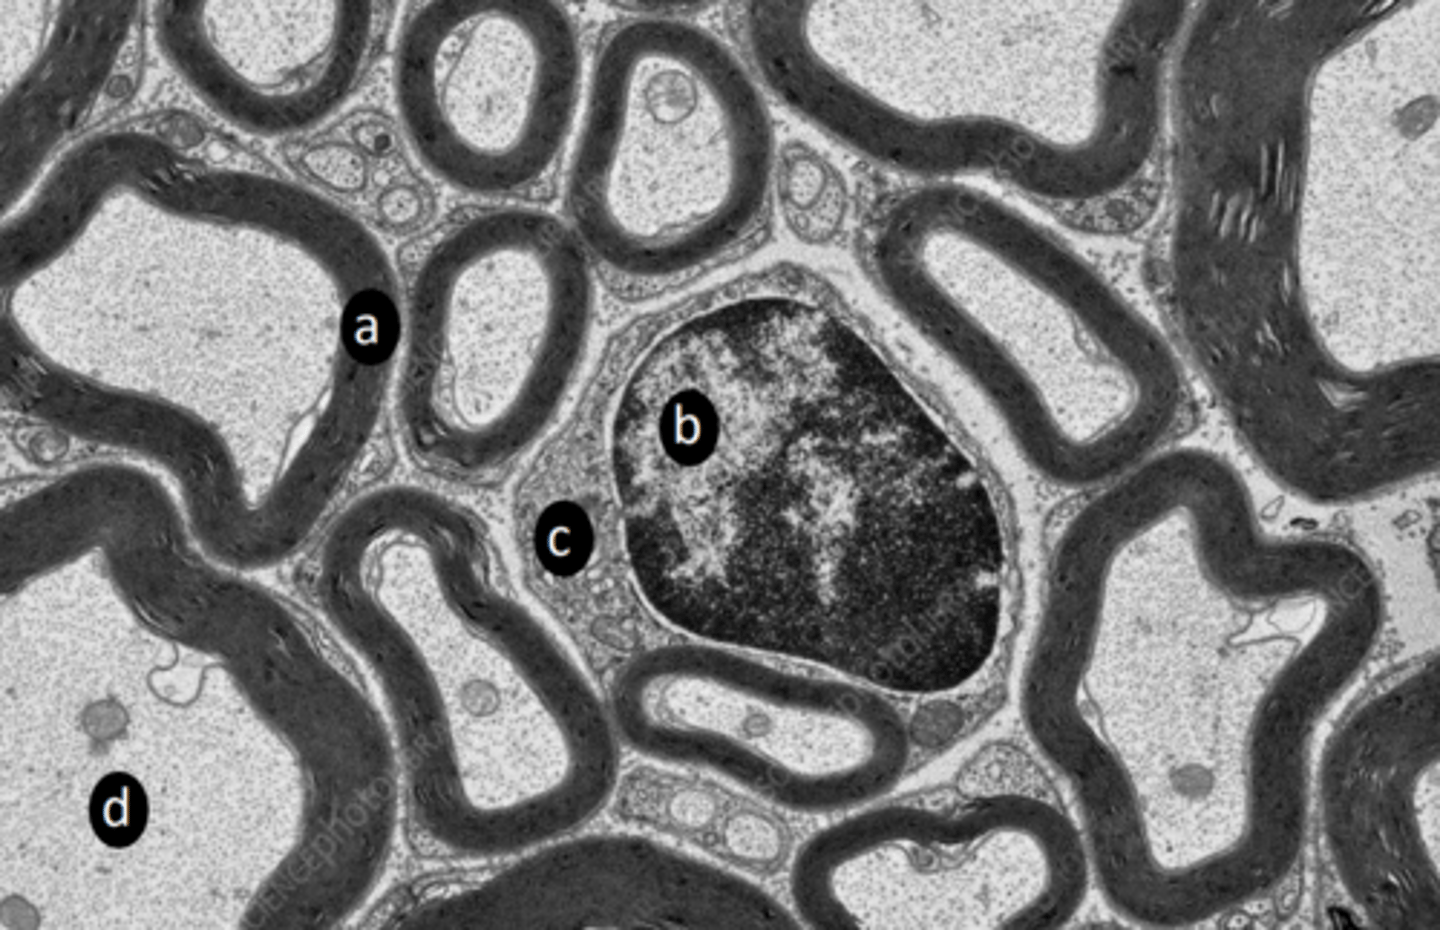

extrafusal myofibers

a: specific tissue type

<p>a: specific tissue type</p>

intrafusal muscle fiber

b: specific tissue type

intrafusal muscle fiber (muscle spindle)

c: specific tissue type

myelin sheath

a: structure

schwann cell nucleus

b: structure

schwann cell cytoplasm

c: structure